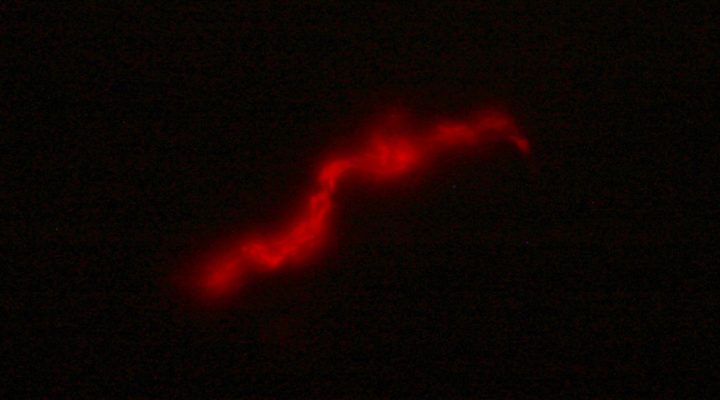

El kit diagnóstico para TB desarrollado por Piuri, equipo y colegas está dotado de un bacteriófago, es decir de un tipo de virus que cuando entra en contacto con la bacteria de la tuberculosis, presente en la muestra de esputo del paciente, expresa una proteína fluorescente lo que permite una lectura directa mediante microscopía de fluorescencia. A futuro plantean automatizar la detección, empleando un microscopio de bajo costo y un programa que por IA pueda contabilizar bacterias fluorescentes en la muestra del paciente reduciendo los tiempos de lectura y la subjetividad del operador.